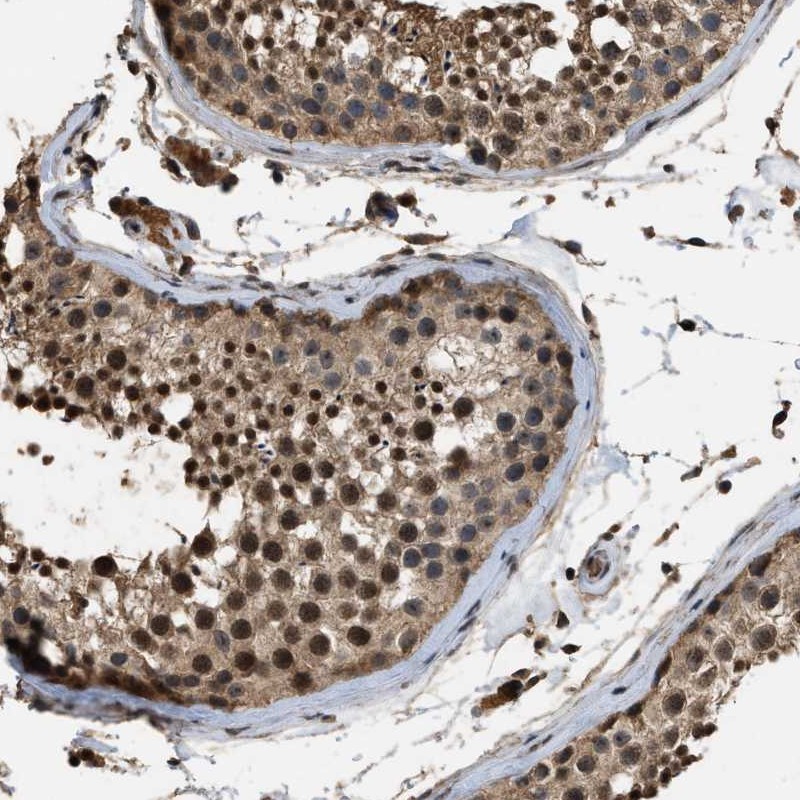

Immunohistochemical staining of human testis shows cytoplasmic and nuclear positivity in cells in seminiferus ducts.